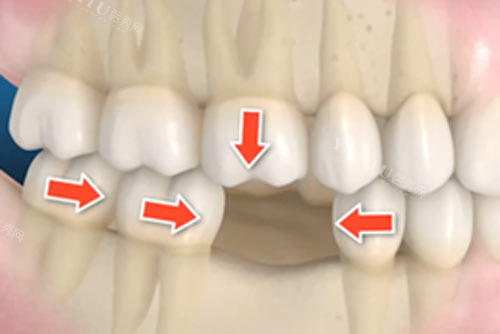

医院是否有专门的儿童牙科部门和适合儿童的诊疗环境;

诊疗项目是否涵盖儿童常见口腔问题的预防和治疗;